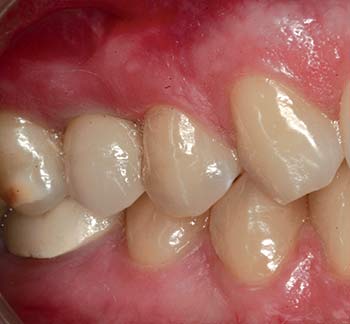

MinerOss Blend cases

grafting for implant placement

MinerOss Blend case 1

MinerOss Blend case provided by Dr. Bach Le